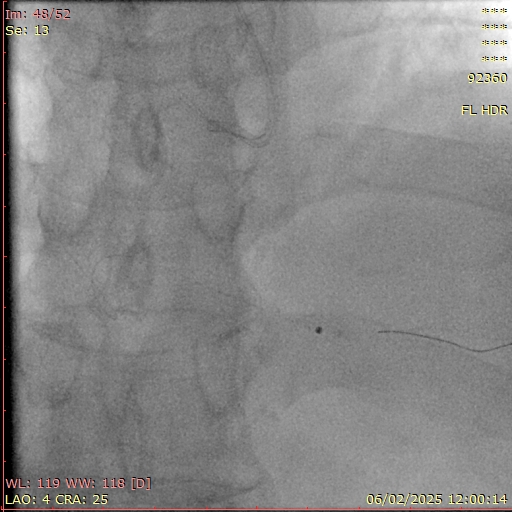

Repeat procedure:Repeat procedure was performed 2 weeks after the index procedure. We used right radial access with AL 0.75/7F guide and 7F guide extension catheter. Angiography revealed TIMI 2 flow to distal RCA, residual stenosis at distal RCA, residual haziness suggestive of thrombus in PDA. IVUS showed partially recanalized consolidated distal RCA thrombus with acceptable luminal size. ELCA was performed with 1.4 mm ELCA catheter under pure saline infusion technique followed by PCI (2.25/29 mm DES) to PDA. Final angiography showed TIMI 3 flow with residual stenosis at distal RCA. FFR LAD 0.84, no further intervention to LAD.